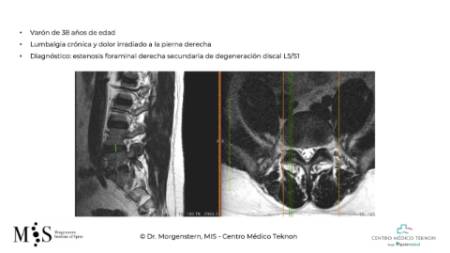

Degenerative disk disease (DDD) is an illness describing an interbody disk (located between two vertebral bodies) that has progressively lost its original height due to the aging process and overloading. A degenerated disk often causes intensive pain in the lower back and buttock area. A complete collapse of the disk height can also lead to foraminal stenosis with an impingement of the exiting nerve roots, causing sciatic pain that radiates to one leg. Hence, disk replacement surgery is indicated for acute and chronic low back pain with or without radiating leg pain.

Clinical Case of an anterior lumbar interbody fusion (ALIF)